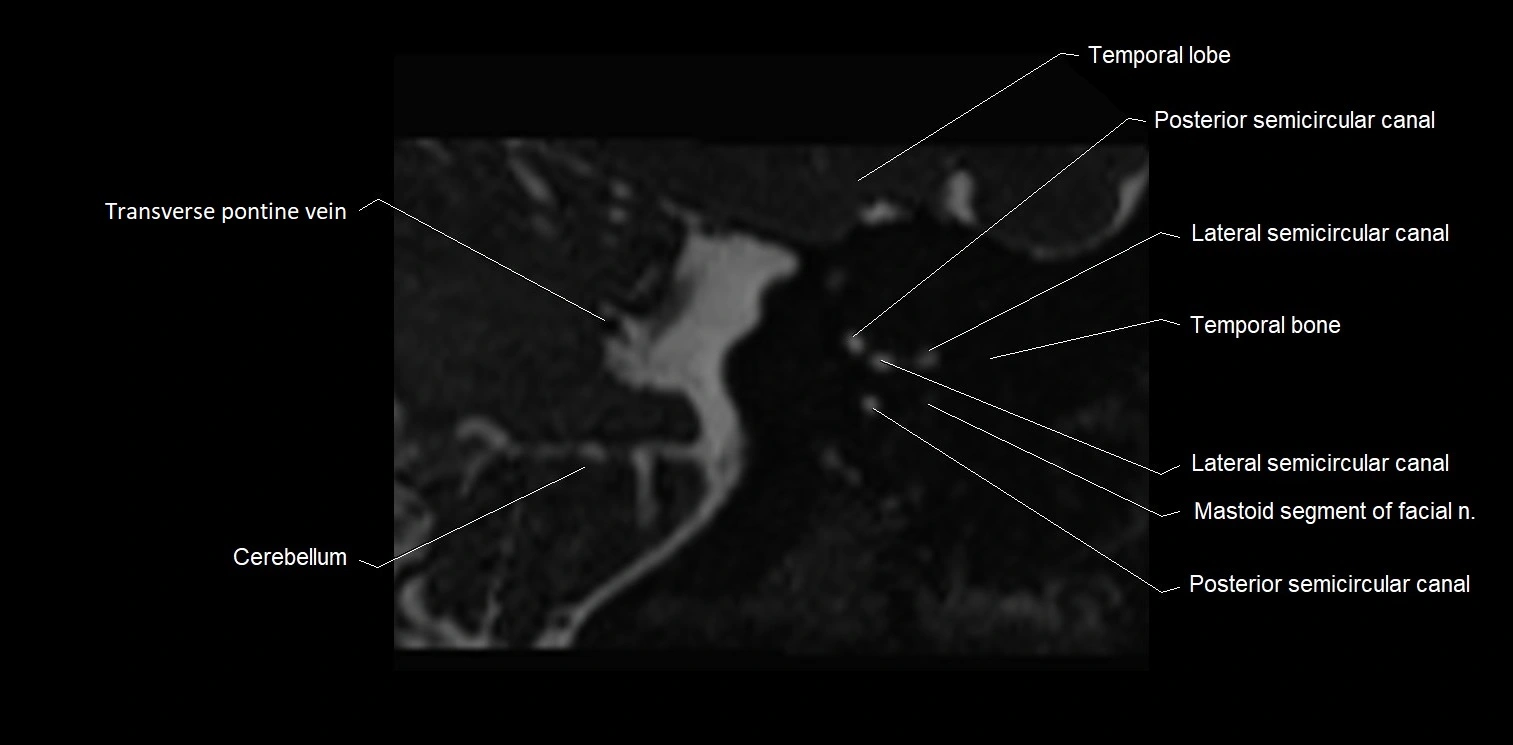

• Best visualized on high-resolution T2-weighted 3D MRI sequences (e.g., FIESTA or CISS)

• Seen as a hypointense (dark) line running from the brainstem at the pontomedullary junction, traversing the prepontine cistern, and entering Dorello’s canal under the petrosphenoidal ligament, then into the cavernous sinus, and finally the orbit